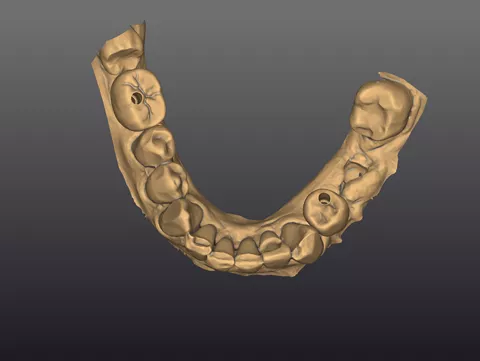

13a. 13b. 13c. The intraoral scan was processed to generate a 3D digital model for prosthetic design.

13a

13b

13c